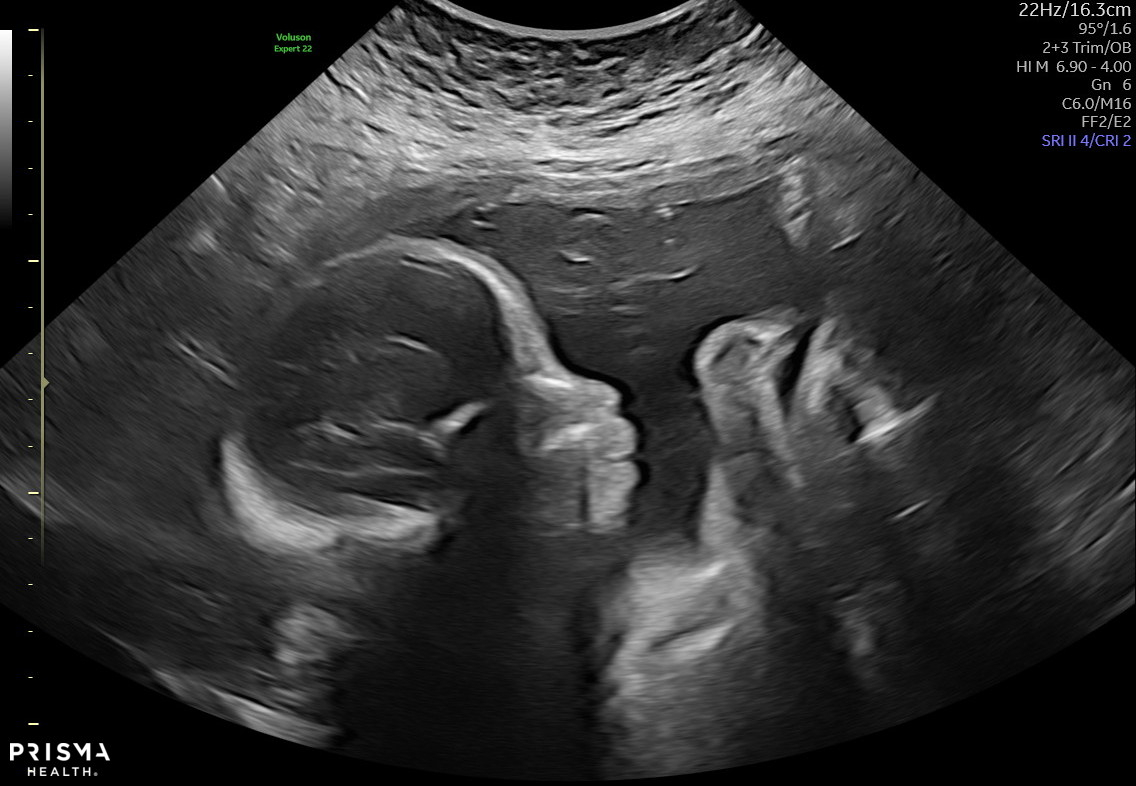

My sweet baby did not sit still AT ALL the entire scan. I felt so bad as the ultrasound tech was training someone and the trainee had such a hard time with my baby 😂 but anyway, here’s my sweet and very active baby boy!!!!